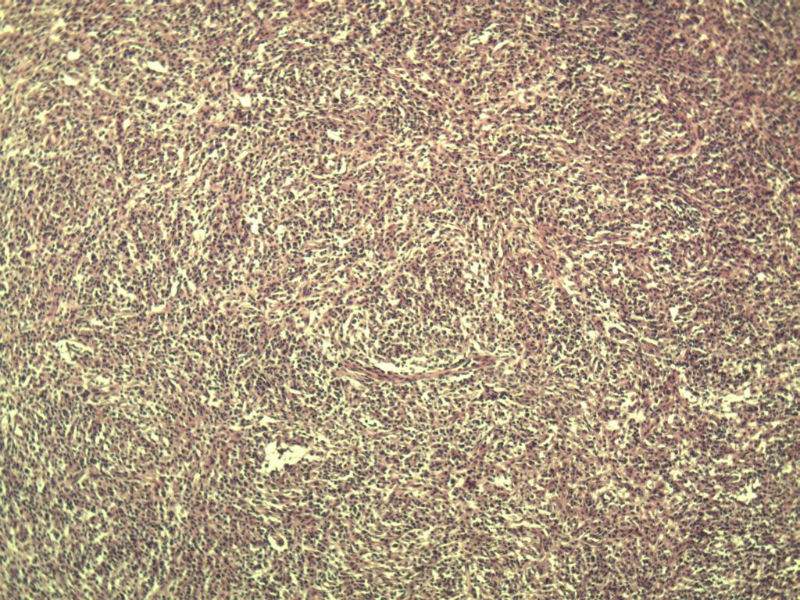

男,38岁,腹股沟 多枚淋巴结活检  直径 0.2-0.5 请各位老师看看 是什么 谢谢了!

"畏寒,发热咳嗽1年,加重伴腹部疼痛2月" 2月前患者感腹部疼痛不适伴大便呈稀大便,量不详,伴腰骶部疼痛,胸片:纵膈及右肺门多发性淋巴结肿大,进一步完善胸部CT:右肺及中叶病变,纵膈及肺门多发淋巴结肿大,结核性可能,脾脏增大,PPD(-),1个月来患者出现中上腹食欲不振,体重进行性消瘦,全身疲乏无力,3天前到医学院就诊,腹部B超:右肝囊肿,胆囊壁毛糙,脾大,胰周多个减弱回声,淋巴结不能除外,腹水,血常规示:WBC16.36x109 /L,N%14.25%,RBC2.63x1012/L ,HGB 66g/L 。右侧腋窝及腹股沟可扪及多枚淋巴结,压痛,无明显粘连。

腹股沟 多枚淋巴结活检图3

副皮质区增生,纤维化显著,细胞呈多形性,有一些多核巨细胞及一些异型细胞,病理性核分裂易见,胞浆红染,散在的小淋巴细胞,T细胞淋巴瘤不能除外,树突细胞肉瘤等鉴别。免疫标记。CD21、CD3、CD5、CD10、CD20、CD79a、PD1、CD68、CXCL13、KI-67、CD68、CD163等,据切片选择。不知对否。

淋巴结正常结构破坏,可见大的异型细胞,上皮样或梭形,恶性肿瘤,依据病史,首先考虑淋巴造血系统疾病,大中小细胞混杂,大细胞多,形态多样,可见多核瘤细胞,除以上考虑外需鉴别间变大、组织细胞肉瘤、指状突/树突细胞肿瘤、HL等,还需排除肉瘤或癌转移,尽管病人年轻,加上ALK、CK、S-100、CD1a。